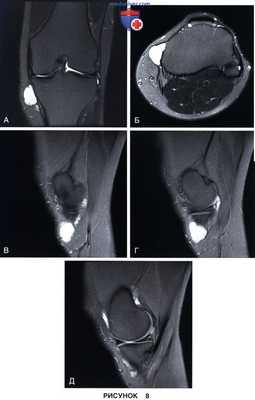

• Перименисковая киста (рис. 8)